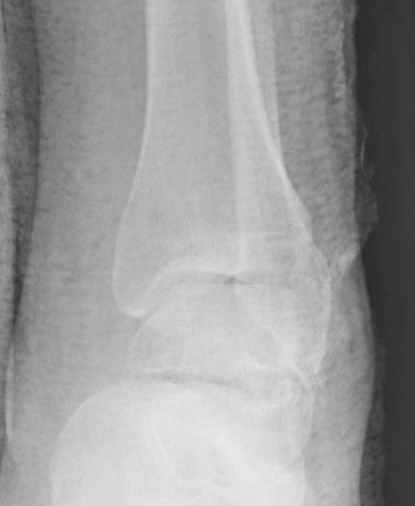

Уважаемые участники русского Ортофорума, поздравляю всех со всеми прошедшими праздниками: Новым годом, Рождеством, Hanukkah, Kwanzaa, желаю участникам всего наилучшего и здоровья.Повреждение таранной кости.Больной 81г автоавария, повреждение таранной кости, здесь снимки. Какие рекомендации?Djoldas Kuldjanov, MDDepartment of Orthopedic SurgerySt. Louis University Medical Center

Вдогонку по поводу перелома таранной кости, больная 81, не страдает диабетом, перелом закрытый, в первый же день поступления ограничились временным наружным фиксатором (как на снимке).

Из-за отека на стопе тактика лечения у всех была

одинаковая: временная наружная фиксация до спадения отека, при изолированных переломах они выписывались домой и через дней 7 госпитализировались на оперативное лечение.

Примеры на снимке...